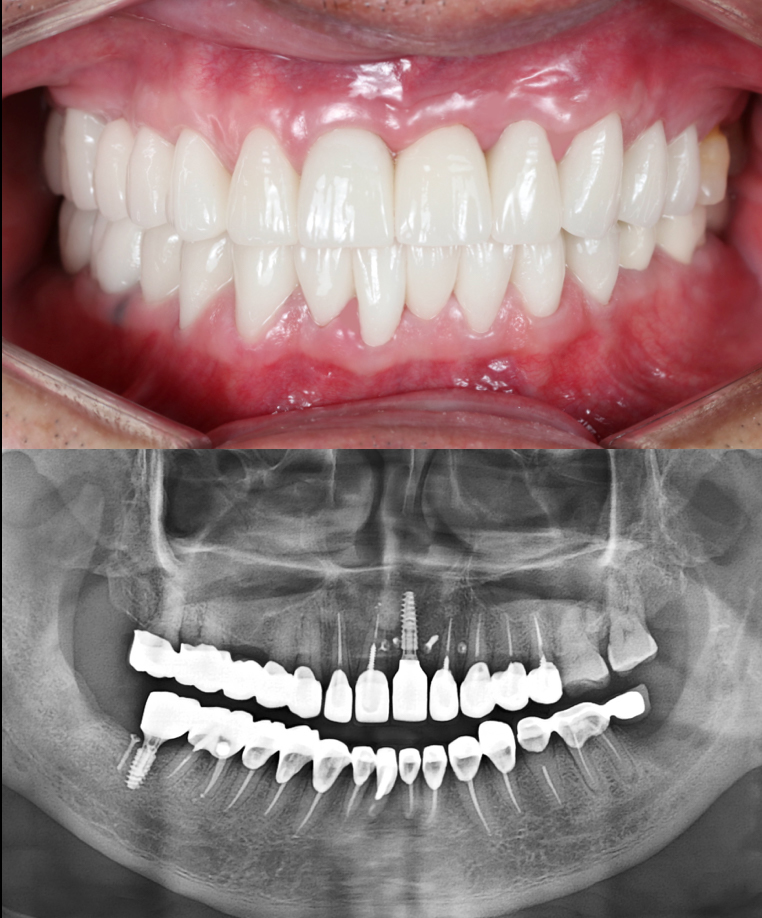

DELAYED IMPLANT - SINGLE

This complex case involved the early implant placement in tooth #21, enhanced with guided bone regeneration to rebuild the buccal architecture for ideal aesthetics and long-term success. To complete the transformation, zirconia crowns were placed on the adjacent two teeth, delivering a perfectly balanced, natural-looking result. Meticulously planned and executed, this case reflects the precision and artistry at Moral Dental Clinic.